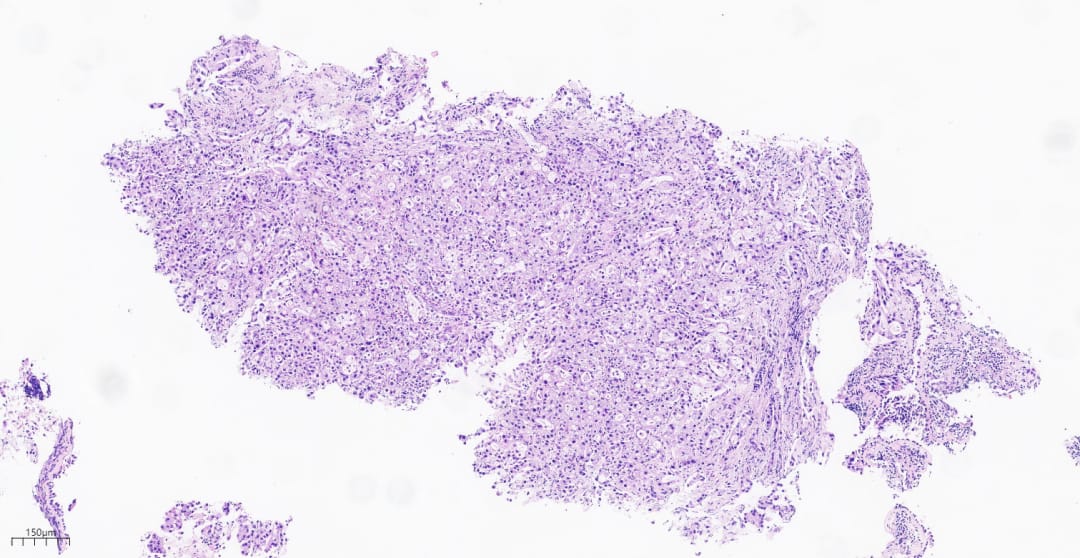

为了明确病变的性质,医生对患者进行了组织病理活检。在显微镜下,病理医生观察到肿瘤细胞形态异常,排列混乱,呈现出低分化腺癌的特征。这些细胞体积较大,细胞核异型明显,显示出高度的恶性潜能。

图2 显微镜下的肿瘤组织呈弥漫片状分布

- 病理形态: 在显微镜下,肿瘤细胞黏附性差,常呈片状或岛状分布,显示出高度的异型性。